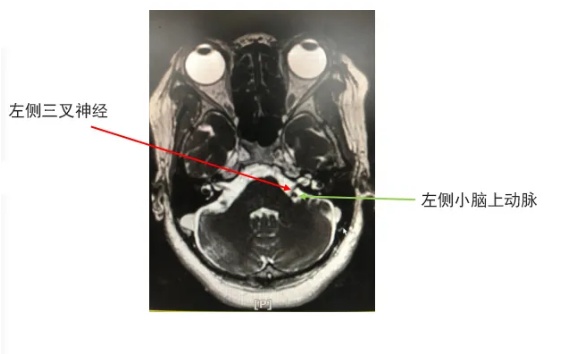

温州医科大学附属第一医院神经外科涂明副主任医师接诊后,耐心细致地分析她的病情、综合研判,初诊考虑三叉神经痛,进一步头颅MRI三叉神经血管成像发现左侧小脑上动脉与三叉神经“亲密接触”,很快,罪魁祸首找到了。